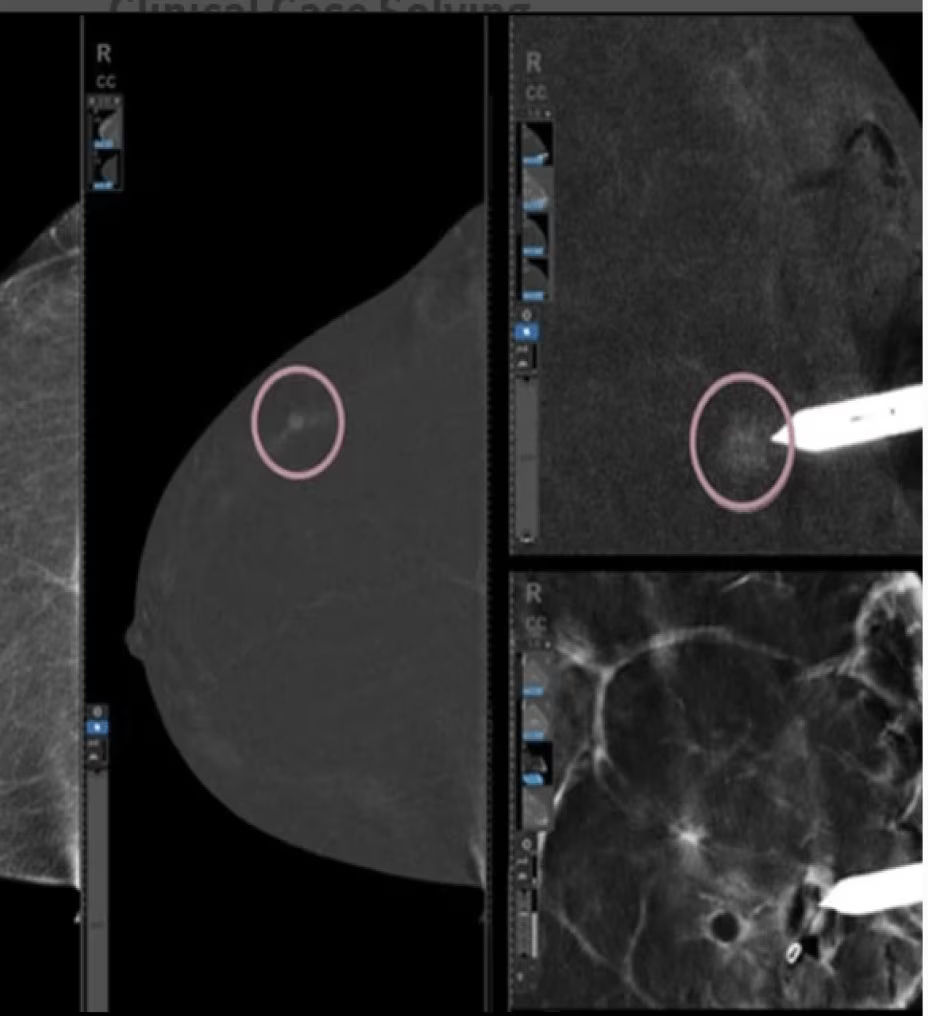

Fast procedure

CEM biopsy can be done within 15 minutes1.

Efficient

Switch to interventional on the same system within your current room in 2 minutes4.